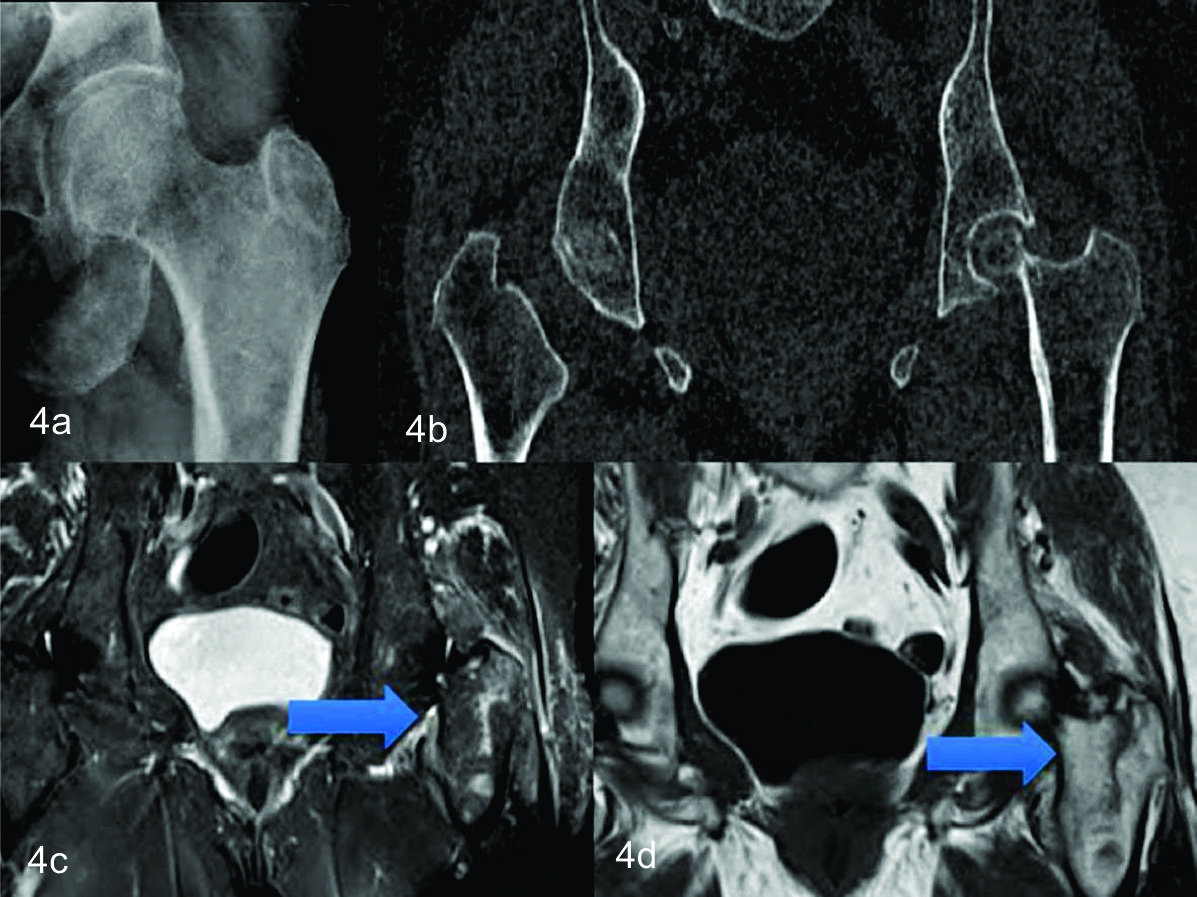

Figura 4

72 años, sexo femenino

a) Radiografía de cadera izquierda frente. b) TC con reconstrucción en el plano coronal de cuello de fémur izquierdo. No se observan trazos de fractura. c) RM fémur proximal izquierdo TSET1. d) STIR, donde se observa fractura hipointensa en T1 y con hiperseñal T2 en STIR, de localización intertrocantérica.